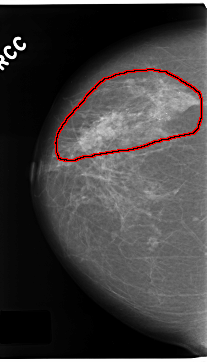

C_0172_1.RIGHT_CC

RIGHT_CC LINES 4696 PIXELS_PER_LINE 2680 BITS_PER_PIXEL 12 RESOLUTION 50 OVERLAY

FILE: C_0172_1.RIGHT_CC.OVERLAY

TOTAL_ABNORMALITIES 1

ABNORMALITY 1

LESION_TYPE CALCIFICATION TYPE PLEOMORPHIC DISTRIBUTION REGIONAL

ASSESSMENT 5

SUBTLETY 5

PATHOLOGY MALIGNANT

TOTAL_OUTLINES 1

BOUNDARY